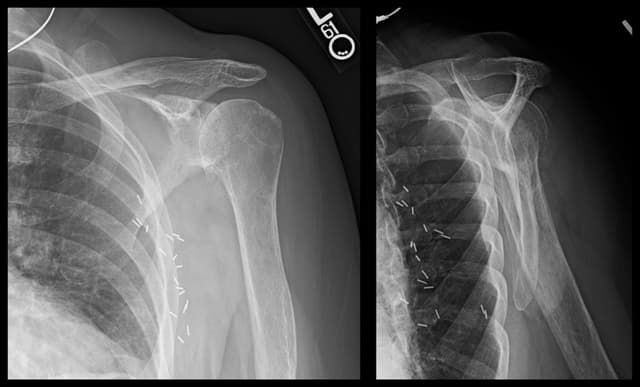

Reverse Shoulder Arthroplasty

Imaging

Pre-op